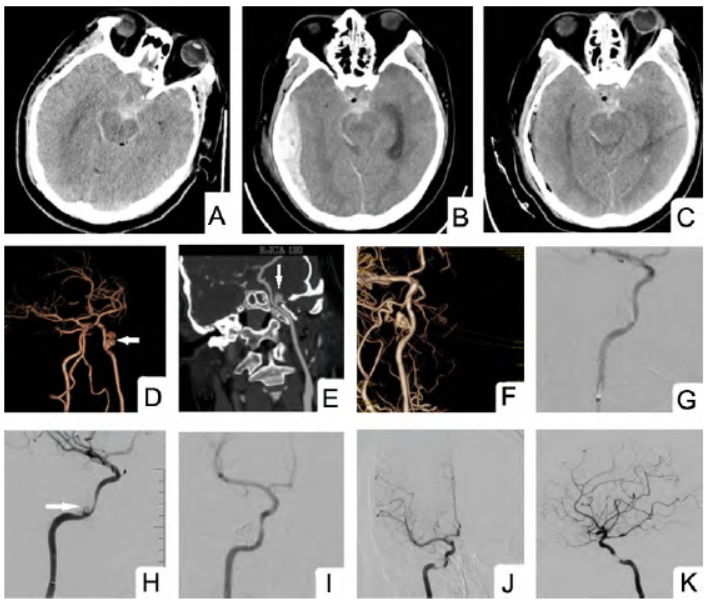

8 min后,突发口鼻流血,约150 ml,并出现意识水平下降,GCS评分5分,血氧饱和度下降,紧急行气管插管。复查颅脑CT发现新增右侧颞顶枕部硬膜外血肿(图1B),CTA示右侧颈内动脉破裂孔段假性动脉瘤(图1D、1E)。

急诊全麻下行假性动脉瘤裸弹簧圈栓塞治疗,术后造影未见动脉瘤显影(图1G);序贯行硬膜外血肿清除术,血肿清除满意(图1C)。术后1d,GCS评分8+T分,复查CT未见新发出血及梗死。术后2 d神志嗜睡状,GCS评分14分,无新发神经功能缺损。术后1周复查脑血管造影

示假性动脉瘤复发(图1H),行覆膜支架植入术,栓塞满意(图1I)。

图1 颈内动脉破裂孔段创伤早期并发假性动脉瘤合并颅内血肿血管内治疗前后影像。A. 入院时颅脑CT显示蛛网膜下腔出血、颅内积气;B. 病情变化后复查CT显示新增硬膜外血肿;C. 硬膜外血肿清除术后复查头部CT显示血肿清除干净;D、E. 裸弹簧圈栓塞前头颈CTA显示颈内动脉破裂孔段动脉瘤(↑示);F. 裸弹簧圈栓塞前3D-DSA显示颈内动脉破裂孔段动脉瘤;G. 裸弹簧圈栓塞术后造影未见动脉瘤显影;H. 弹簧圈栓塞术后1周复查DSA发现动脉瘤复发(↑示);I. Willis支架置入术后造影未见动脉瘤显影,载瘤血管通畅;J、K. Willis支架置入术后1年复查DSA未见动脉瘤复发,载瘤血管通畅